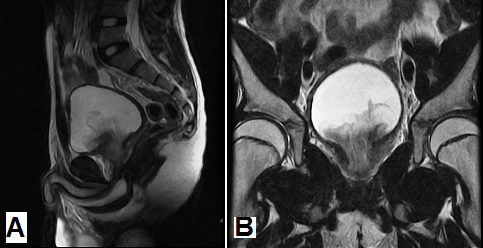

Surgical Management of Genitourinary Rhabdomyosarcoma

- The management of genitourinary rhabdomyosarcoma has gradually evolved from radical extirpative surgery to organ-sparing surgery with the aim of preserving organ function and improving the patient’s quality of life without compromising oncological outcomes.

- Primary resection of genitourinary rhabdomyosarcoma should not be attempted unless the tumor can be safely and completely resected in its entirety without considerable morbidity or loss of organ function.

- Symphysiotomy significantly facilitates the exposure and visibility to the prostate and posterior urethra in children with bladder or prostate rhabdomyosarcoma. Nerve-sparing technique should be the standard of care provided that local cancer control is not compromised.

- Residual masses post chemotherapy do not necessarily mean residual tumor. Maturing rhabdomyoblasts found on post-chemotherapy specimens can be managed with continued chemotherapy and observation with repeated imaging and biopsies.